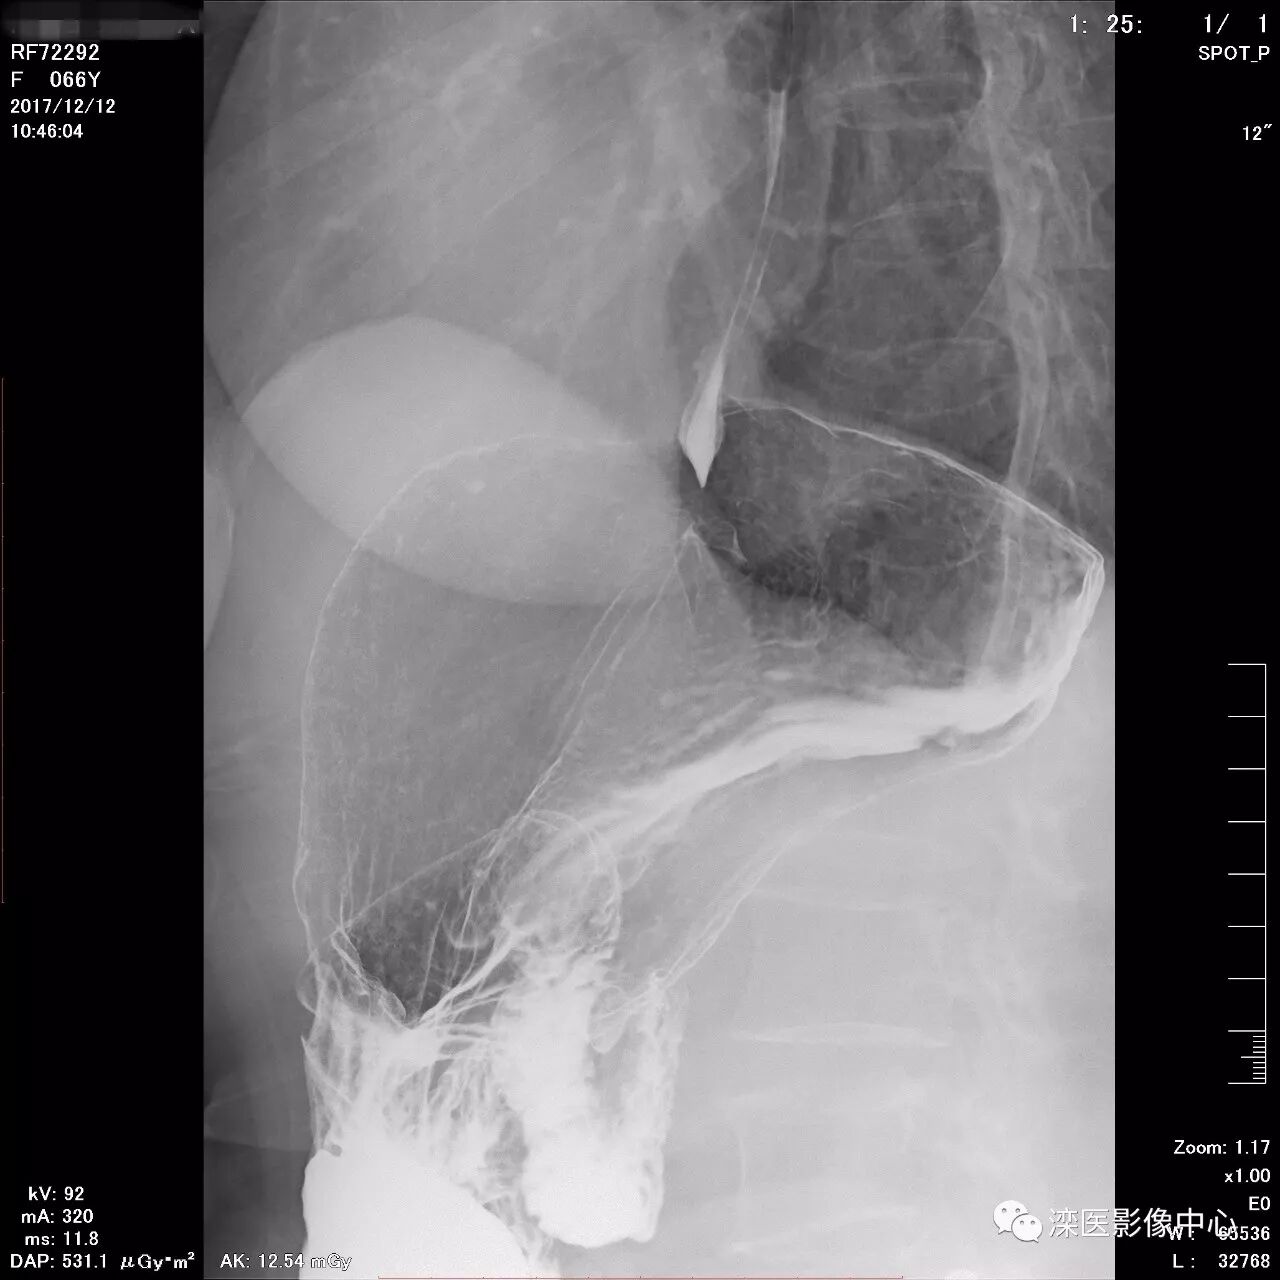

正位,显示食管、贲门及喉咽部的粘膜像)

(左前斜位,显示食管、贲门的粘膜像

(右前斜位,显示食管、贲门的粘膜像)

(以上图像是患者立位+卧位,通过变换体位,多角度显示了贲门胃底、胃体、胃大弯、胃小弯、胃窦、幽门及十二指肠球部、降部、水平部、升部的粘膜像和充盈像。本例患者女性,66岁,此次检查可以清晰显示胃小区结构,检查中发现患有慢性胃炎、胃下垂、十二指肠降部憩室)